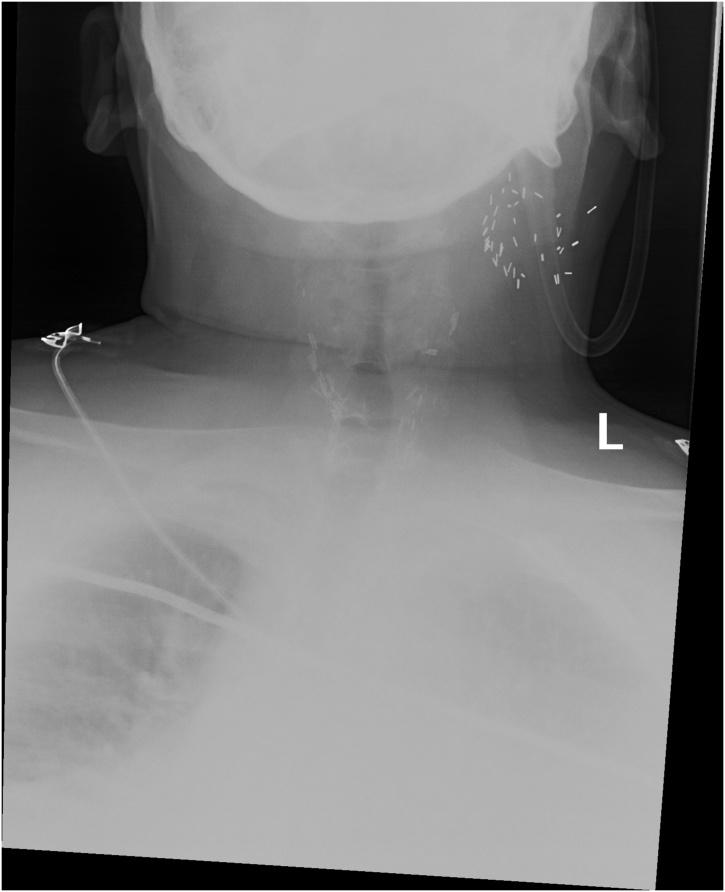

A case report of serotype W135 epiglottitis in the United States and review of twelve adult cases of meningococcal epiglottitis.

https://cdn.ncbi.nlm.nih.gov/pmc/blobs/4132/6249400/8c60e25c526e/gr1.jpg